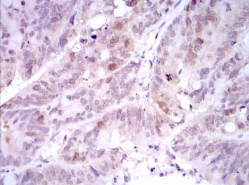

IHC    1/100 - 1/500